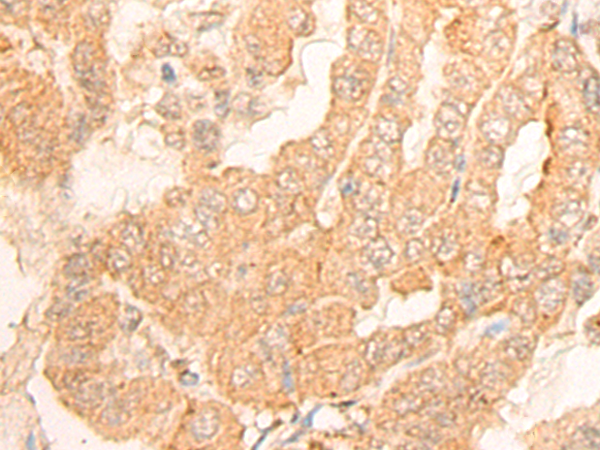

IHC Positive control: |

Human thyroid cancer; |

IHC Recommended dilution: |

25-100 |